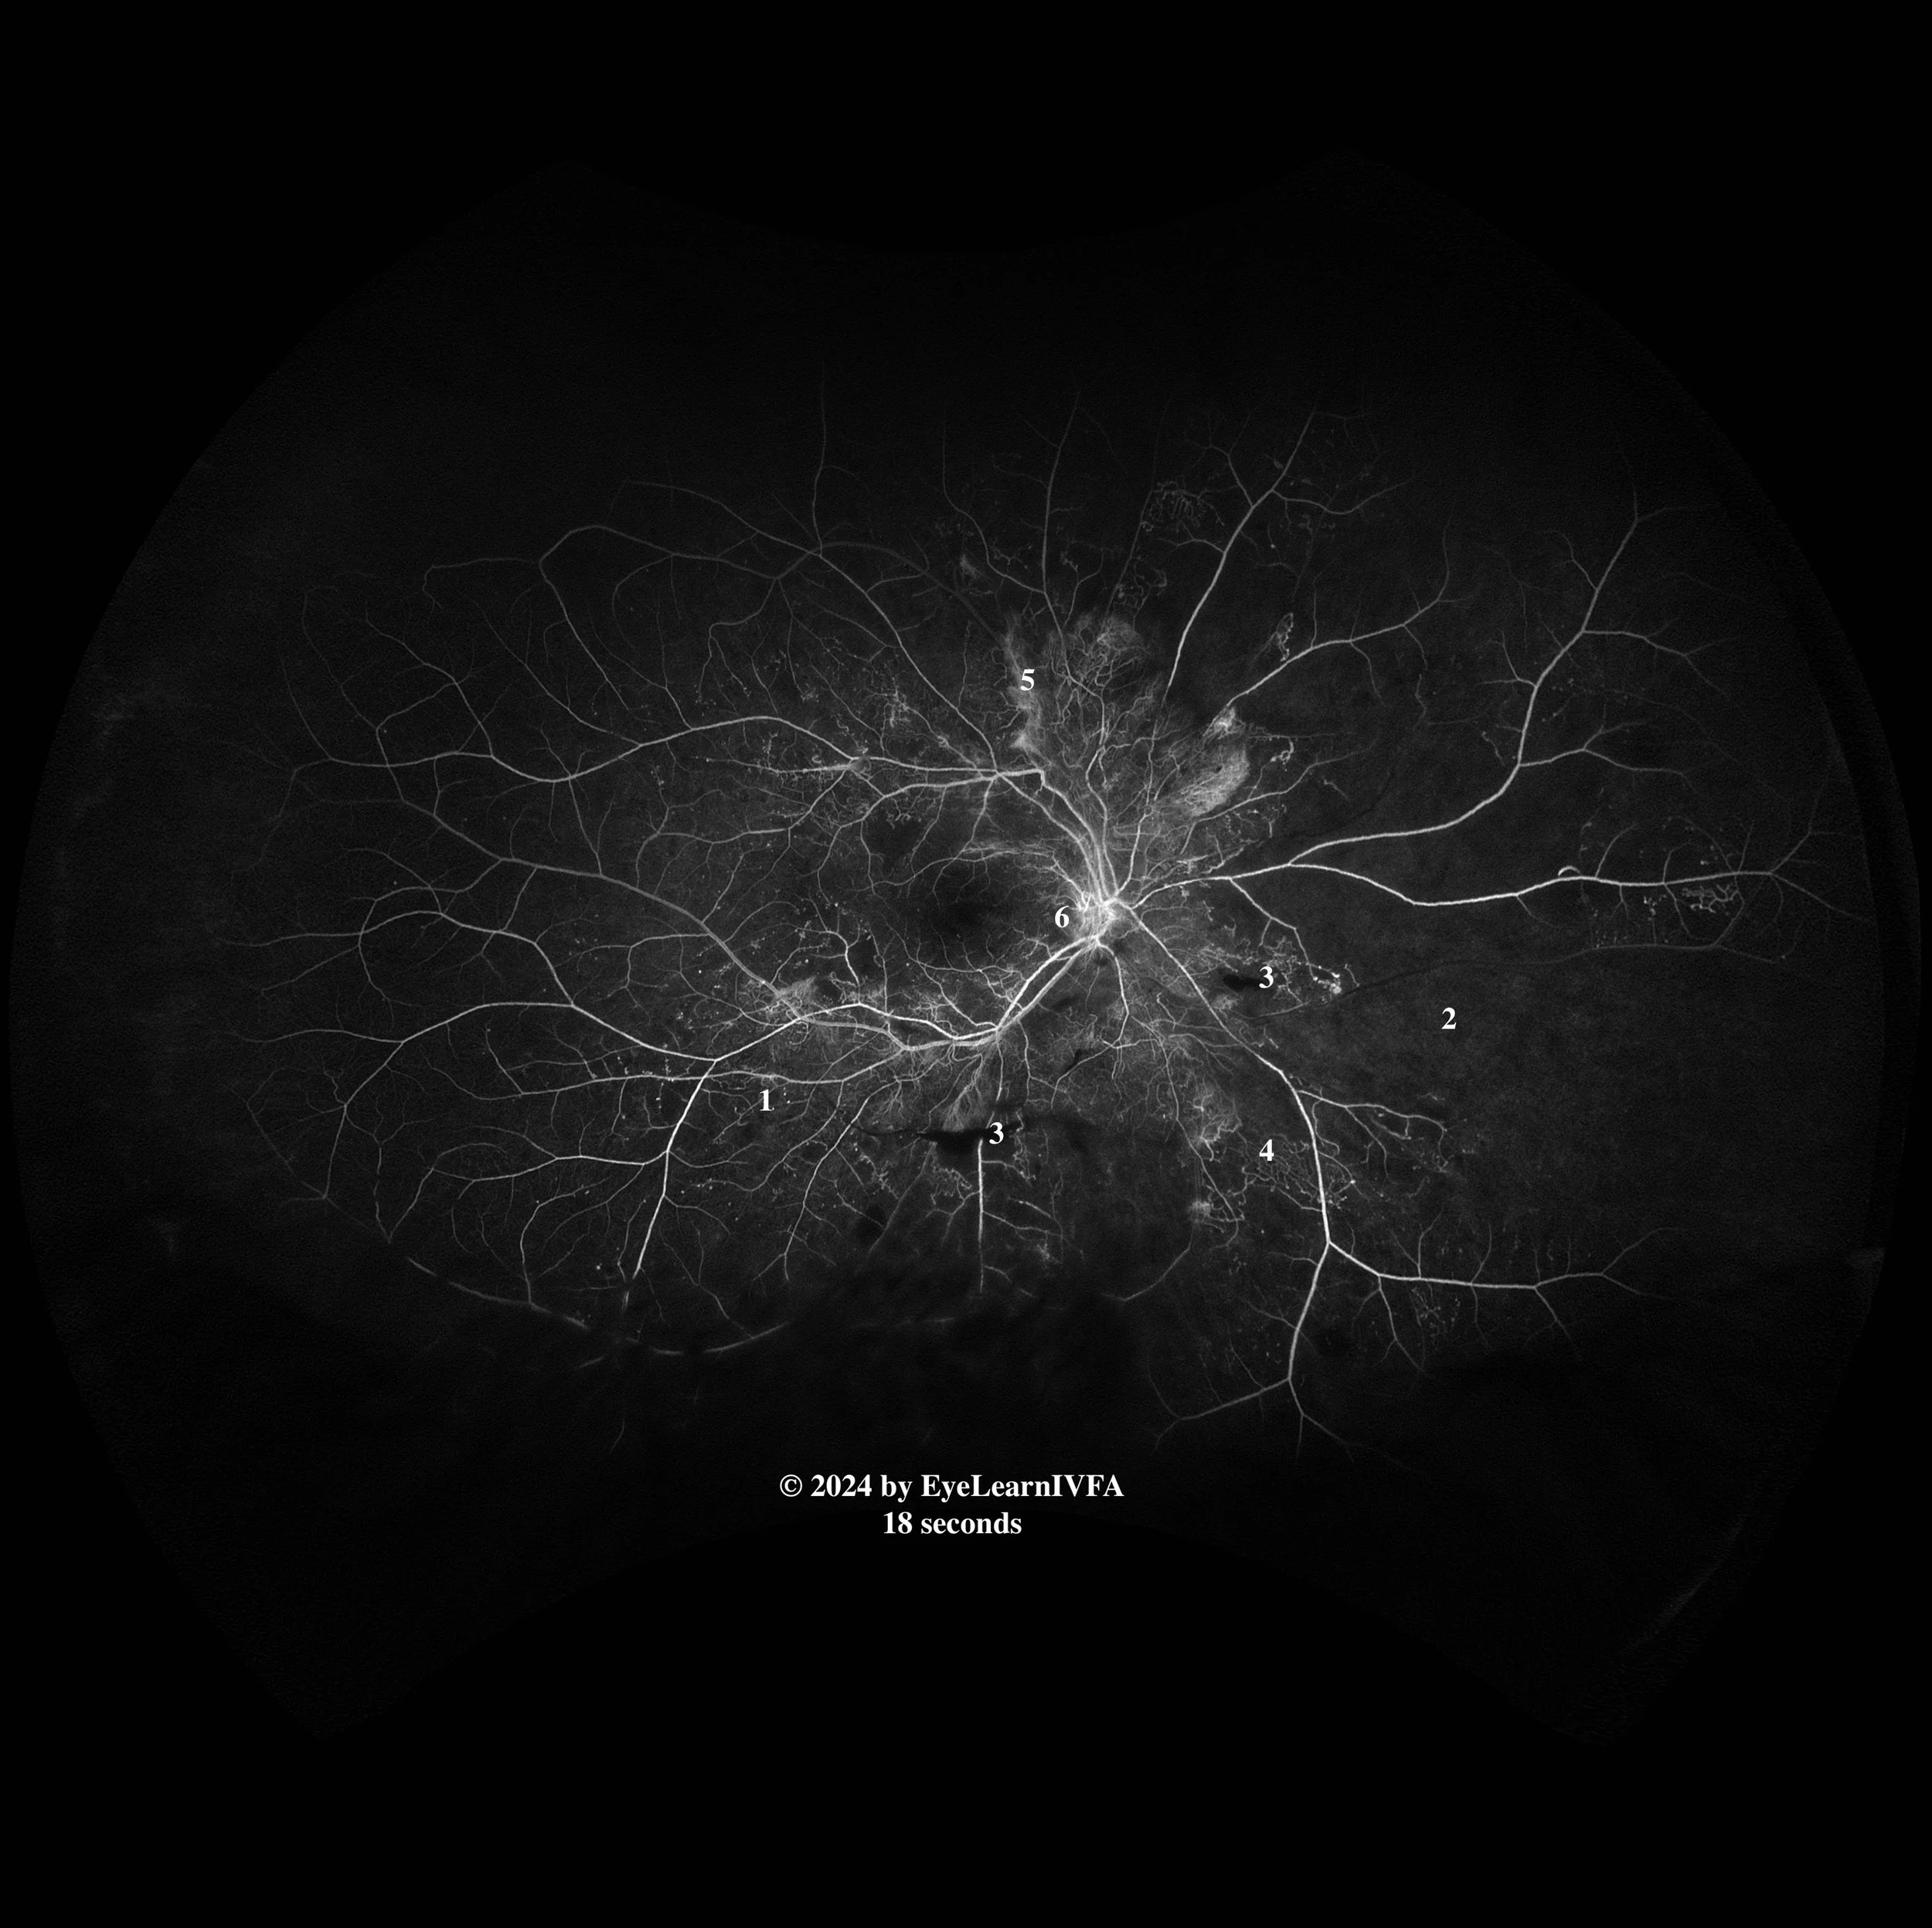

IVFA Transit: Right Eye

• IVFA at 18 seconds

Early to Mid Arteriovenous Phase

Key Features:

• Several hyperfluorescent pinpoint spots surrounding the vasculature due to leakage from microaneurysms (1).

• Nasally, reduced choroidal fluorescence from capillary drop out (2).

• Hypofluorescence secondary to blockage from pre-retinal/vitreous hemorrhage (3).

• Intraretinal microvascular abnormalities (IRMAs) - dilated/tortuous vessels that have minimal leakage (4).

• Hyperfluorescence with indistinct borders in the posterior pole secondary to neovascularization elsewhere (NVE) (5).

• Hyperfluorescence at the disc due to neovascularization of the disc (NVD) (6).